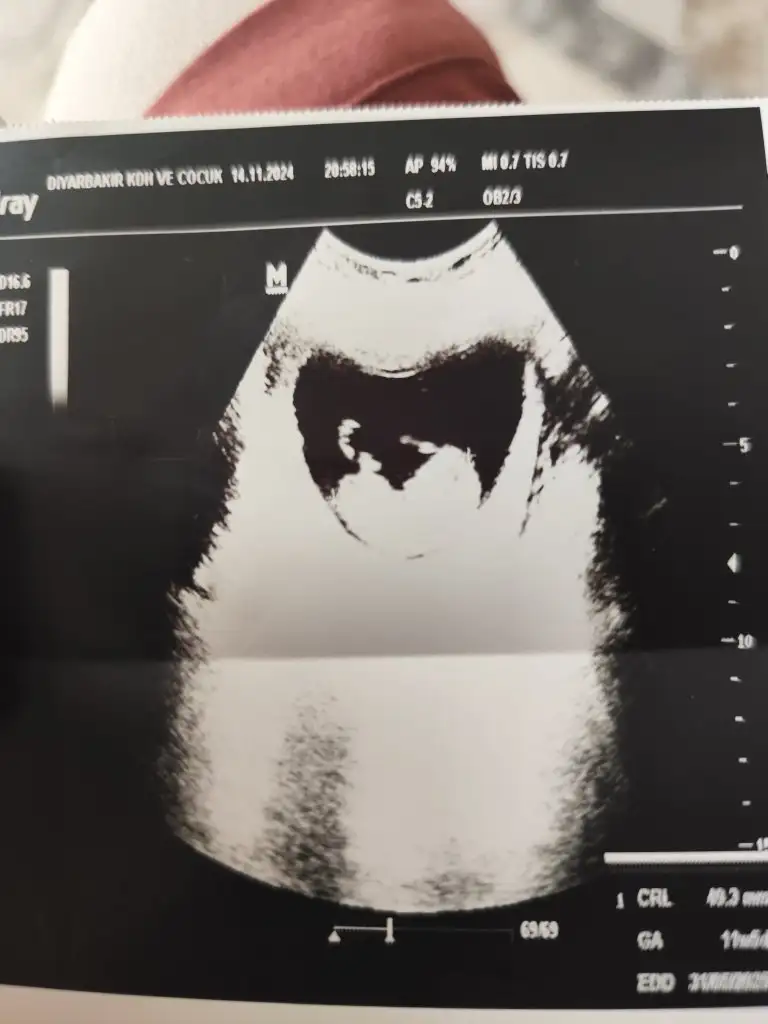

ay sizinkiyle benim bebiş benziyodu içime bi umut düştüBugun gittim %90 kiz dedi

Merhaba benim için de cinsiyet tahmini yapabilir misinizBebek gelişirken cinsel organında bir açı oluşur orada da bir açı var açı dikeyse erkek yatay ise kızdır oradaki açı biraz yatay sizin nub teorisi. Benim kızımda da tutmuştu bu teori

Sata göre 11 haftalıkKaç haftalık bebek canım

Sata göre 11 haftalık